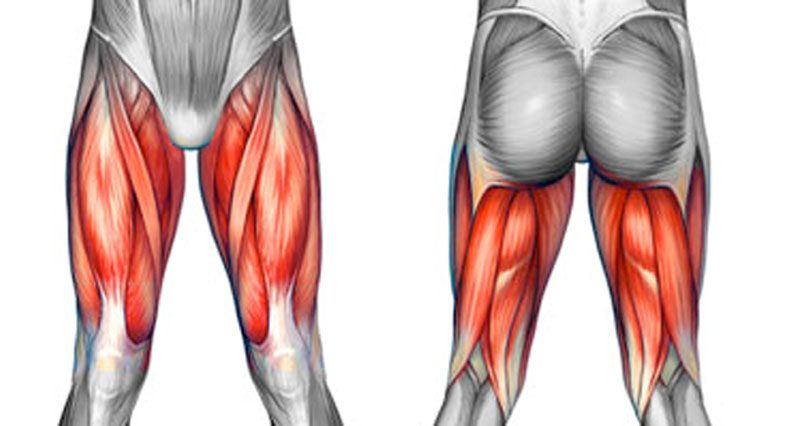

당산정형외과 당산역정형외과 당산동정형외과 여의도정형외과 합정정형외과 목동정형외과 영등포정형외과 영등포구청정형외과 선유도정형외과)안녕하세요^^ 도수치료를 담당하고 있는 물리치료사 박호동입니다. 이번시간에는 허벅지 근육을 유연하게 관리하는 법에 대해 알려드릴까 합니다. 엉덩이와 허벅지로 이어지는 근육을 부드럽게 하는 것은 ​ 다리질환에 도움이 될 뿐만 아니라, 골반과 척추에도 도움이 됩니다. 근육을 유연하게 하기 위해서는 스트레칭 운동을 꾸준히 하면 된다는 사실은 누구나 아실 겁니다. 하지만 평소에 운동을 자주 하지 않는 분들에게는 무리한 스트레칭이 독이 될 수 있어요. 이럴때, 스트레칭을 보다 쉽게 접근하기 위한 방법을 알려드릴려고 합니다. 바로 동작검사-자극-스트레칭 방법이에요. 동작이 뻣뻣한지 검사해..